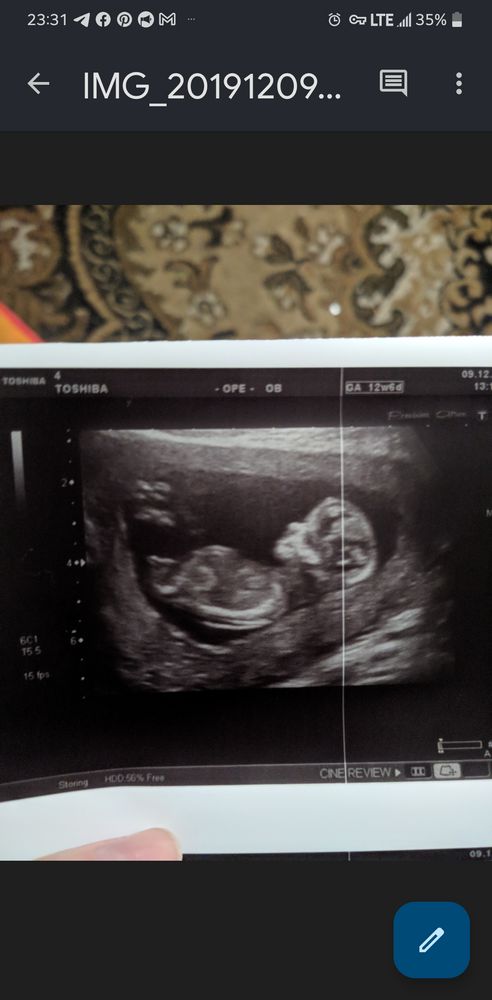

Изображение Юлия Sonnце, смотрите на примере моей дочи,о чем я

07.10.2022

Enot v teme , ну, конечно, я вижу у Вас тут половой бугорок девичий))) Но в 15 недель, как у автора, там уже не бугорок... Да и мне на таком сроке в обе б-ти показывали с другого ракурса, со стороны попы)) потому и сомнения по снимку Валерии. В общем, Бог с ним. Главное, чтобы малыш был здоров, а его половая принадлежность - дело десятое😊